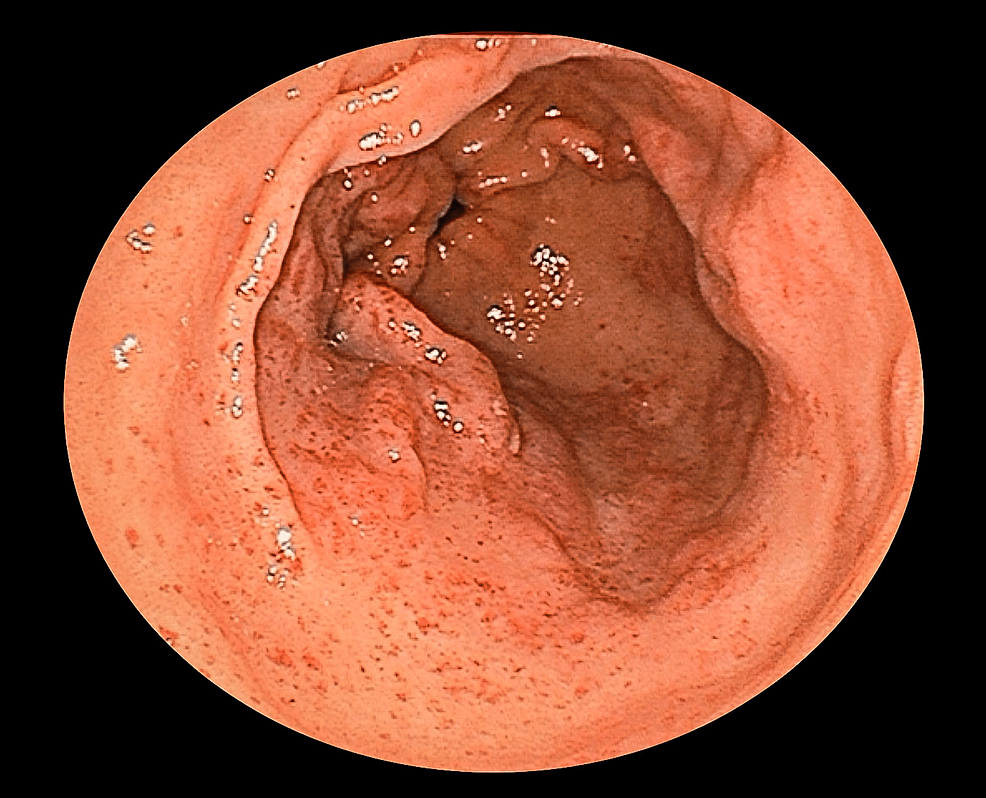

Gastric antral vascular ectasia observed on upper gastrointestinal Vascular Ectasia Examples Vascular lesions include acquired lesions (eg, pyogenic granuloma, nevus araneus) and those that are present at birth or arise shortly after birth. (1) zonated/lobular growth, (2) bland. Telangiectases need to be distinguished from other vascular conditions, including blood vessel tumours such as infantile haemangioma and angiomas that arise in adults; In general, the following morphologic features in a vascular tumor. Vascular Ectasia Examples.

Gastric antral vascular ectasia. Endoscope view of the antrum (final Vascular Ectasia Examples This review describes various vascular anomalies, in accordance with issva classification and terminology; Vascular lesions include acquired lesions (eg, pyogenic granuloma, nevus araneus) and those that are present at birth or arise shortly after birth. Telangiectasias are small dilated blood vessels found anywhere on the body, but commonly seen on the face around the nose, cheeks, and chin. (1) zonated/lobular. Vascular Ectasia Examples.